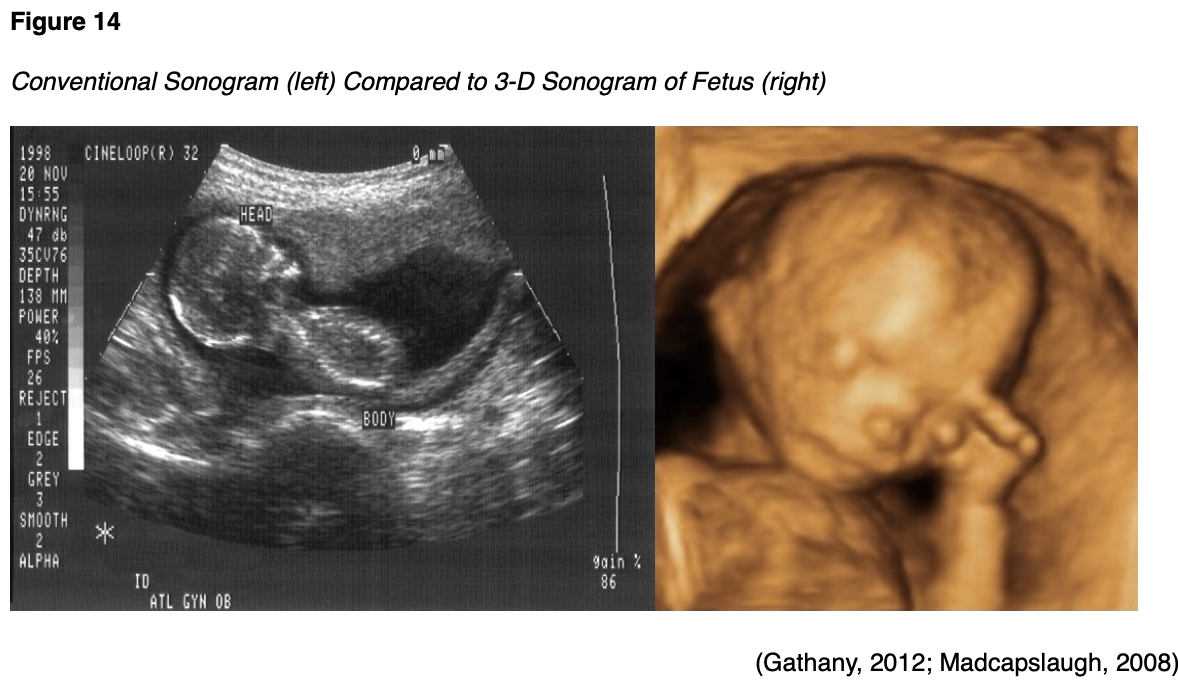

Ultrasound